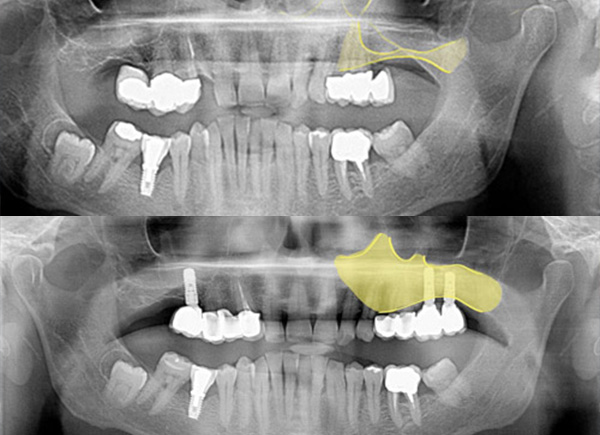

The first image shows the state of the bone before the sinus lift treatment. In the areas where the implants will subsequently be added there are only 2-4 mm of bone.

From the next image we can see how after the sinus lift procedure the new bone is now 12 mm high.

Six months after the procedure two Straumann implants are inserted (12 and 10 mm) and three months later a dental bridge is placed on them.